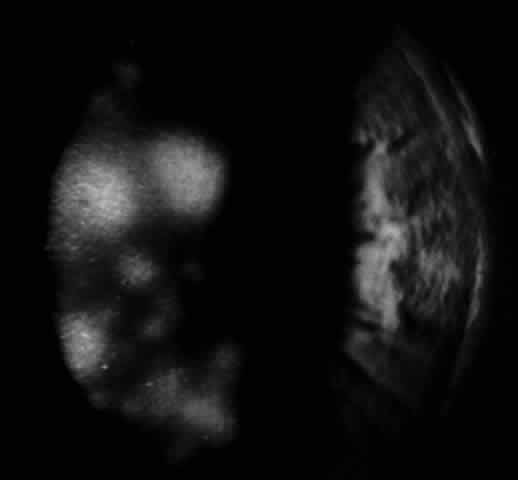

In 1986, Matoba and associates reported 7 patients with purported EBV stromal keratitis, but only 3 of the patients had clinical symptoms of IM or evidence of recent seroconversion.69 In one of the patients, heterophil antibody-positive IM preceded by 1 week the onset of chronic multifocal keratitis. When the authors first examined the patient in referral 9 months later, they found multiple, discrete, anterior stromal opacities in the patient's left eye. In another patient, bilateral, patchy, deep peripheral infiltrative keratitis and a fourfold decrease in antibody against EBV viral capsid antigen were documented at the time of referral 5 months after an “infectious mononucleosis-like illness” associated with bilateral red eyes and photophobia. In another patient, the authors state that IM preceded subepithelial infiltrative keratitis in the left eye by 1 month. When examined 8 months after onset of the keratitis, the patient's left cornea showed features of multifocal anterior stromal and deep peripheral stromal keratitis. Although the other 4 patients in this series did not show evidence of recent EBV seroconversion, their keratitis appeared similar to that of the patients with documented IM. On clinical grounds alone, Matoba and associates postulated that the development of EBV keratitis did not depend on recent EBV infection, but could occur in the chronic carrier state. To summarize the authors' findings in the combined group of 7 patients, the interstitial keratitis appeared in 4 patients as unilateral, multifocal, discrete, sharply demarcated, anterior stromal opacities, 0.1 to 2 mm in diameter, with either a blotchy pleomorphic (Fig. 2) or granular ringlike appearance (Fig. 3), in two patients as bilateral, multifocal, full-thickness or deep stromal peripheral infiltrates reminescent of luetic keratitis (Fig. 4), and in 1 patient with features of both. No patient tested had showed serologic evidence of acute systemic HSV or adenovirus infection. Both patients with keratitis restricted to the peripheral cornea had bilateral disease but lacked serologic evidence for syphilis (nonreactive MHA-TP). Five patients had mild or moderate corneal stromal vascularization. Two patients showed corneal epithelial granularity overlying the stromal opacities.

Fig. 2. Blotchy pleomorphic multifocal anterior stromal corneal infiltrates in a 25-year-old woman. (Matoba AY, Wilhelmus KR, Jones DB: Epstein-Barr viral stromal keratitis. Ophthalmology 93:746, 1986)

Fig. 3. Sharply demarcated ring opacities of the anterior corneal stroma in an 11-year-old boy. (Matoba AY, Wilhelmus KR, Jones DB: Epstein-Barr viral stromal keratitis. Ophthalmology 93:746, 1986)

Fig. 4. Multifocal deep peripheral corneal stromal infiltrates in a 17-year-old man. (Matoba AY, Wilhelmus KR, Jones DB: Epstein-Barr viral stromal keratitis. Ophthalmology 93:746, 1986)